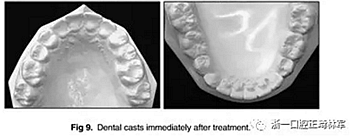

治療的總體目標得以實現(xiàn)(圖8)??傊委煏r間為36個月。面部方面表現(xiàn)出充分的唇閉合和愉快的微笑。切牙運動后有一些唇縮回。覆蓋和覆合良好,并且上下牙弓相協(xié)調(diào)(圖9)。I類磨牙關(guān)系得以實現(xiàn)。左側(cè)后牙反合得以矯正。下頜第二磨牙成功直立。